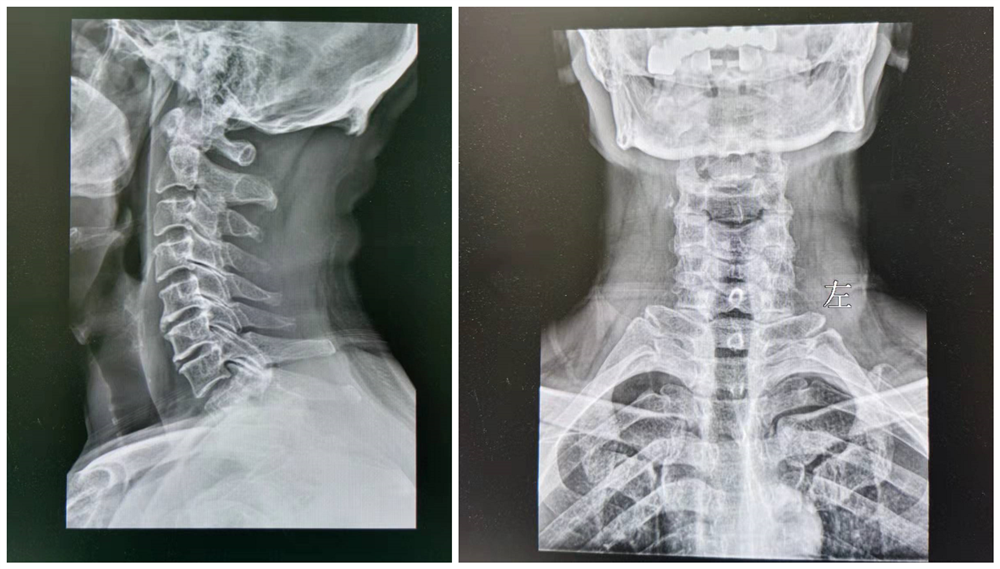

病人:29岁 , 诊断出颈源性高血压患者

看这两张片子 , 大家能看出点什么来?可能不仔细看 , 大家感觉 , 其实没有什么毛病呀!大家应该听过一句话 , 失之毫厘谬以千里!身体关节部位一丁点的变动 , 其实都是有可能影响你身体的真凶!就比如现在这个患者 , 年龄并不大 , 但是家里环境并不是太好 , 又感觉自己是青壮年 , 所以是以工作为主 , 生活很没有规律 , 再加上长期的抽烟喝酒 , 业务陪客户 , 所以年纪轻轻就高血压!

后来就有一位医生提出来 , 比如 , 颈源性高血压患者 , 如果将患者的各个颈椎骨矫正 , 就是通过正骨的方式将骨骼矫形好 , 然后通过针灸调理局部肌肉经脉 , 通过推针刺激穴位 , 通过中药内服 , 中药外敷熏蒸能不能将颈椎局部调理好!